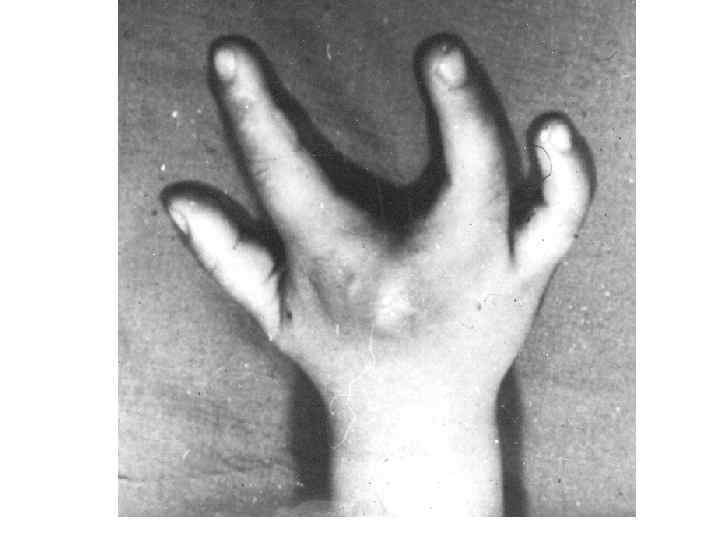

Омыртқалардың дамуының варианттары және аномалиялары 1 -омыртқалардың доғасының аномалиялары: -оң және сол жақ доғалардың біркіпеуі -доғалардың омыртқа денесімен бірікпеуі -омыртқа доғасының жетілмеуі немесе оның жоқ болуы 2 -омыртқалардың өсінділердің аномалиялары: -қосымша өсінділер -қылқан өсінділерінің бөліктенуі -буын өсінділерінің жетілмеуі және деформациясы 3 -омыртқалардың денесінің деформациясы 4 -омыртқалардың әрбір бөліктеріндегі, олардың сандары не көбейіп, не азайып өзгеруі • 5 -люмбализация • 6 -сакрализация • 7 -омырқалардың көптеген синостоздары • • •

8 -сколиоз 9 -омыртқалардың доғаларының бірікпеуі 10—спондилез Атавистикалық белгілер: 1 -күрең тәрізді тері өсіндісі 2 -құйымшақ омыртқаларының көп болуы 3 -күрең тәрізді өсінділер. Олар жұмсақ тіндерден тұрады да, терімен жабылады. Адам қартайған кезде омыртқалар омыртқа арасындағы дискалардың және олардың пішіндері өзгеруіне байланысты қозғаласы нашарлайды: олар серпінділігін жоғалтып үлкен кеуде қисығын түзеді – кәрілік қисығы.